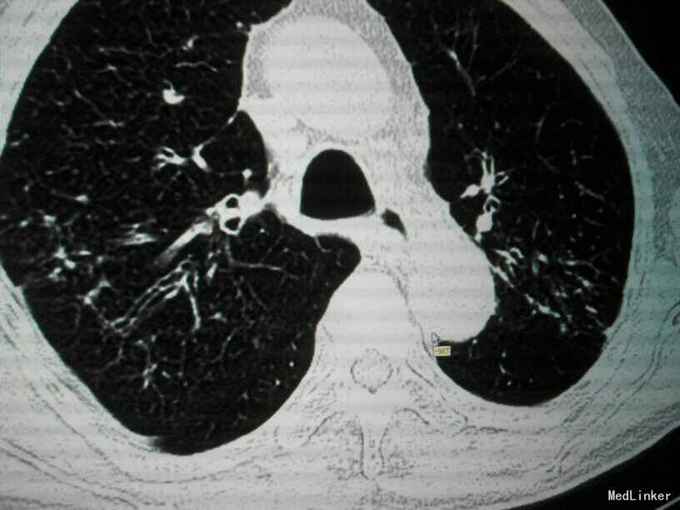

查体:唇指发绀,桶状胸,肋间隙增宽,双肺叩诊呈过清音,双肺呼吸音粗,可闻及散在干湿性啰音,未闻及明显湿性罗音,呼气延长,心腹阴性,双下肢轻度水肿。 辅助检查:入院后血气分析 PH 7.41 PCO2 43mmHg,PO2 73mmHg,BE 2.7mmol/L SO2:96%;心电图:室性早搏;胸片:符合慢支合并双肺炎症;肺CT示1.两肺多发支气管扩张并感染2.两肺间质纤维化,两侧胸膜增厚;心脏彩超:肺动脉压增高,肺动脉略宽;痰培养:肺炎克雷伯杆菌亚种;

诊断:慢阻肺急性发作;支气管扩张并感染;肺间质纤维化;慢性肺心病 治疗经过:抗炎:哌拉西林他唑巴坦;化痰:羧甲司坦口服液+盐酸氨溴索针;解痉平喘:多索茶碱,复方异丙托溴铵雾化溶液+布地奈德雾化混悬剂,雾化吸入;扩冠、减轻心脏负荷:硝酸甘油针;利尿:拖拉塞米针;3日后停硝酸甘油,改单硝酸异山梨酯缓释片口服,后患者出现胸闷、胸痛、气短症状加重,请心内科会诊后,给予呋塞米20㎎,隔日1次口服;螺内酯片20㎎,1日1次;替米沙坦片40㎎ 1日1次;美托洛尔6.25㎎;氯化钾缓释片 0.5g,1日2次;并给予抗血小板聚集、调脂、稳定斑块等治疗;治疗10天后,患者受凉后出现畏寒、发热,侧体温38.1℃,停哌拉西林他唑巴坦,改为盐酸莫西沙星针0.4g,1日1次,其余治疗同前;治疗3天后患者体温恢复正常,偶有咳嗽,咳少量白色黏痰,症状好转,出院。